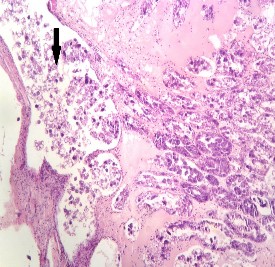

Hình 3.5: Tổ chức mô của tôm bị AHPND

(Mũi tên đen: Các tế bào máu tập hợp ở khoảng giữa ống gan tụy và nhiễm khuẩn)

Kết quả gây nhiễm vi khuẩn V.parahaemolyticus 12.020 trên tôm thẻ chân trắng khỏe với các nghiệm thức khác nhau cho thấy rằng vi khuẩn này có khả năng gây hoại tử gan tụy cấp. Đặc điểm mô bệnh học tôm mắc phải AHPND theo định nghĩa của Lightner và cộng sự (2012) và hướng dẫn nhận biết dấu AHPND (Cục Thú y, 2012) là cấu trúc mô gan tụy bị biến đổi, có hiện tượng suy giảm tế bào B, F và R, các tế gan thoái hóa rơi vào lòng ống và xuất hiện các cụm vi khuẩn trong vùng bị hoại tử (Hình 3.5). Trong nghiên cứu của Nguyễn Trọng Nghĩa và cộng sự (2013) khi phân lập và xác định khả năng gây hoại tử cuả vi khuẩn Vibrio parahaemolyticus trên địa bàn tỉnh Bạc Liêu cho thấy vi khuẩn này có khả năng gây hoại tử gan tụy cấp khi gây cảm

nhiễm thực nghiệm trên tôm thẻ chân trắng ở nghiệm thực 105 cfu/g (sau 9

ngày và 106 cfu/g (sau 6 ngày) với dấu hiệu bệnh lý và mô bệnh học tương tự thí nghiệm mà chúng tôi đã thực hiện.